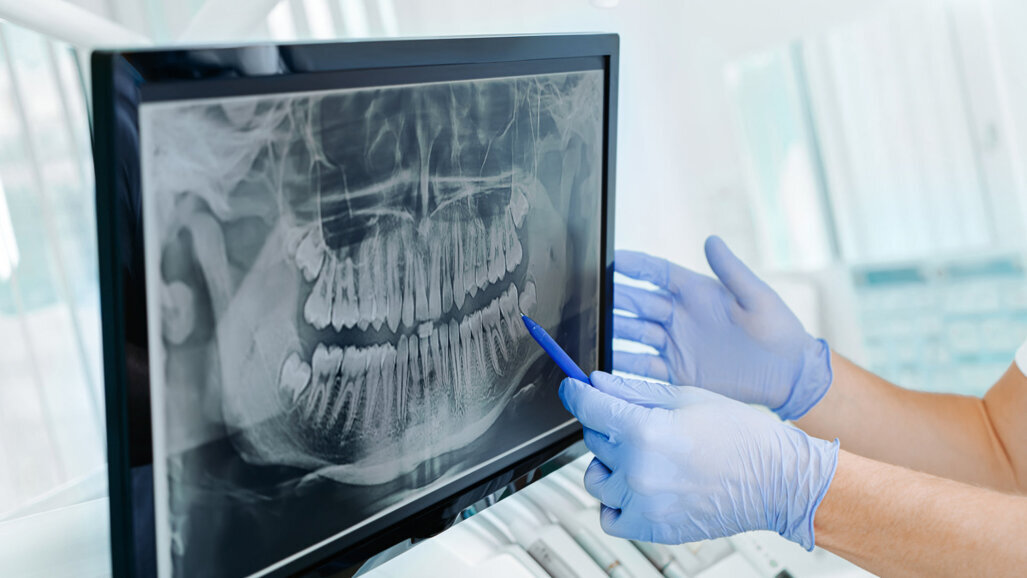

ESKISEHIR, TÜRKEI – Frühere Studien haben die Verwendung von KI zur Erkennung von Karies, Wurzelfrakturen und apikalen Läsionen untersucht. Forschungen auf dem Gebiet der Parodontologie gibt es jedoch nur begrenzt. Nun wurde auf dem EuroPerio10 eine Forschungsarbeit1 vorgestellt, bei der ein Deep-Learning-Algorithmus parodontale Erkrankungen anhand von 2D-Bissflügel-Röntgenaufnahmen erkennt.

Diese Studie bewertete die Fähigkeit von Deep Learning, einer Art KI, zur Bestimmung des parodontalen Status in Bissflügel-Röntgenaufnahmen. Die Studie verwendete 434 Bissflügel-Röntgenaufnahmen von Patienten mit Parodontitis. Die Bildverarbeitung wurde mit der u-net-Architektur durchgeführt, einem konvolutionellen neuronalen Netzwerk, das zur schnellen und präzisen Segmentierung von Bildern verwendet wird. Ein erfahrener Facharzt wertete die Bilder zusätzlich mit der Segmentierungsmethode aus. Die Bewertungen umfassten den gesamten Alveolarknochenverlust um die unteren und oberen Zähne herum.

Das neuronale Netzwerk identifizierte 859 Fälle von Alveolarknochenverlust, 2.215 Fälle von horizontalem Knochenverlust, 340 Fälle von vertikalem Knochenverlust, 108 Furkationsdefekte und 508 Fälle von Zahnstein. Der Erfolg des Algorithmus beim Identifizieren von Defekten wurde mit der Beurteilung des Arztes verglichen und als Sensitivität, Präzision und F1-Wert angegeben, der der gewichtete Durchschnitt von Sensitivität und Präzision ist. Für Empfindlichkeit, Präzision und F1-Score ist 1 der beste Wert und 0 der schlechteste.

Die Sensitivitäts-, Präzisions- und F1-Score-Ergebnisse für den gesamten Alveolarknochenverlust betrugen 1, 0,94 bzw. 0,96. Die entsprechenden Werte für horizontalen Knochenverlust waren 1, 0,92 bzw. 0,95, während AI keinen vertikalen Knochenverlust identifizieren konnte. Für Zahnstein waren die Sensitivitäts-, Präzisions- und F1-Score-Ergebnisse 1,0, 0,7 bzw. 0,82 und für Furkationsdefekte waren die entsprechenden Werte 0,62, 0,71 bzw. 0,66.

Dr. Yavuz sagte: „Unsere Studie zeigt, dass KI in der Lage ist, viele Arten von Defekten aus 2D-Bildern zu erkennen, die bei der Diagnose von Parodontitis hilfreich sein könnten. Umfassendere Studien sind auf größeren Datensätzen erforderlich, um den Erfolg der Modelle zu steigern und ihre Verwendung auf 3D-Röntgenaufnahmen auszudehnen.“ Er schloss: „Diese Studie gibt einen Einblick in die Zukunft der Zahnmedizin, in der KI Bilder automatisch auswertet und Zahnärzten hilft, Krankheiten früher zu diagnostizieren und zu behandeln.“